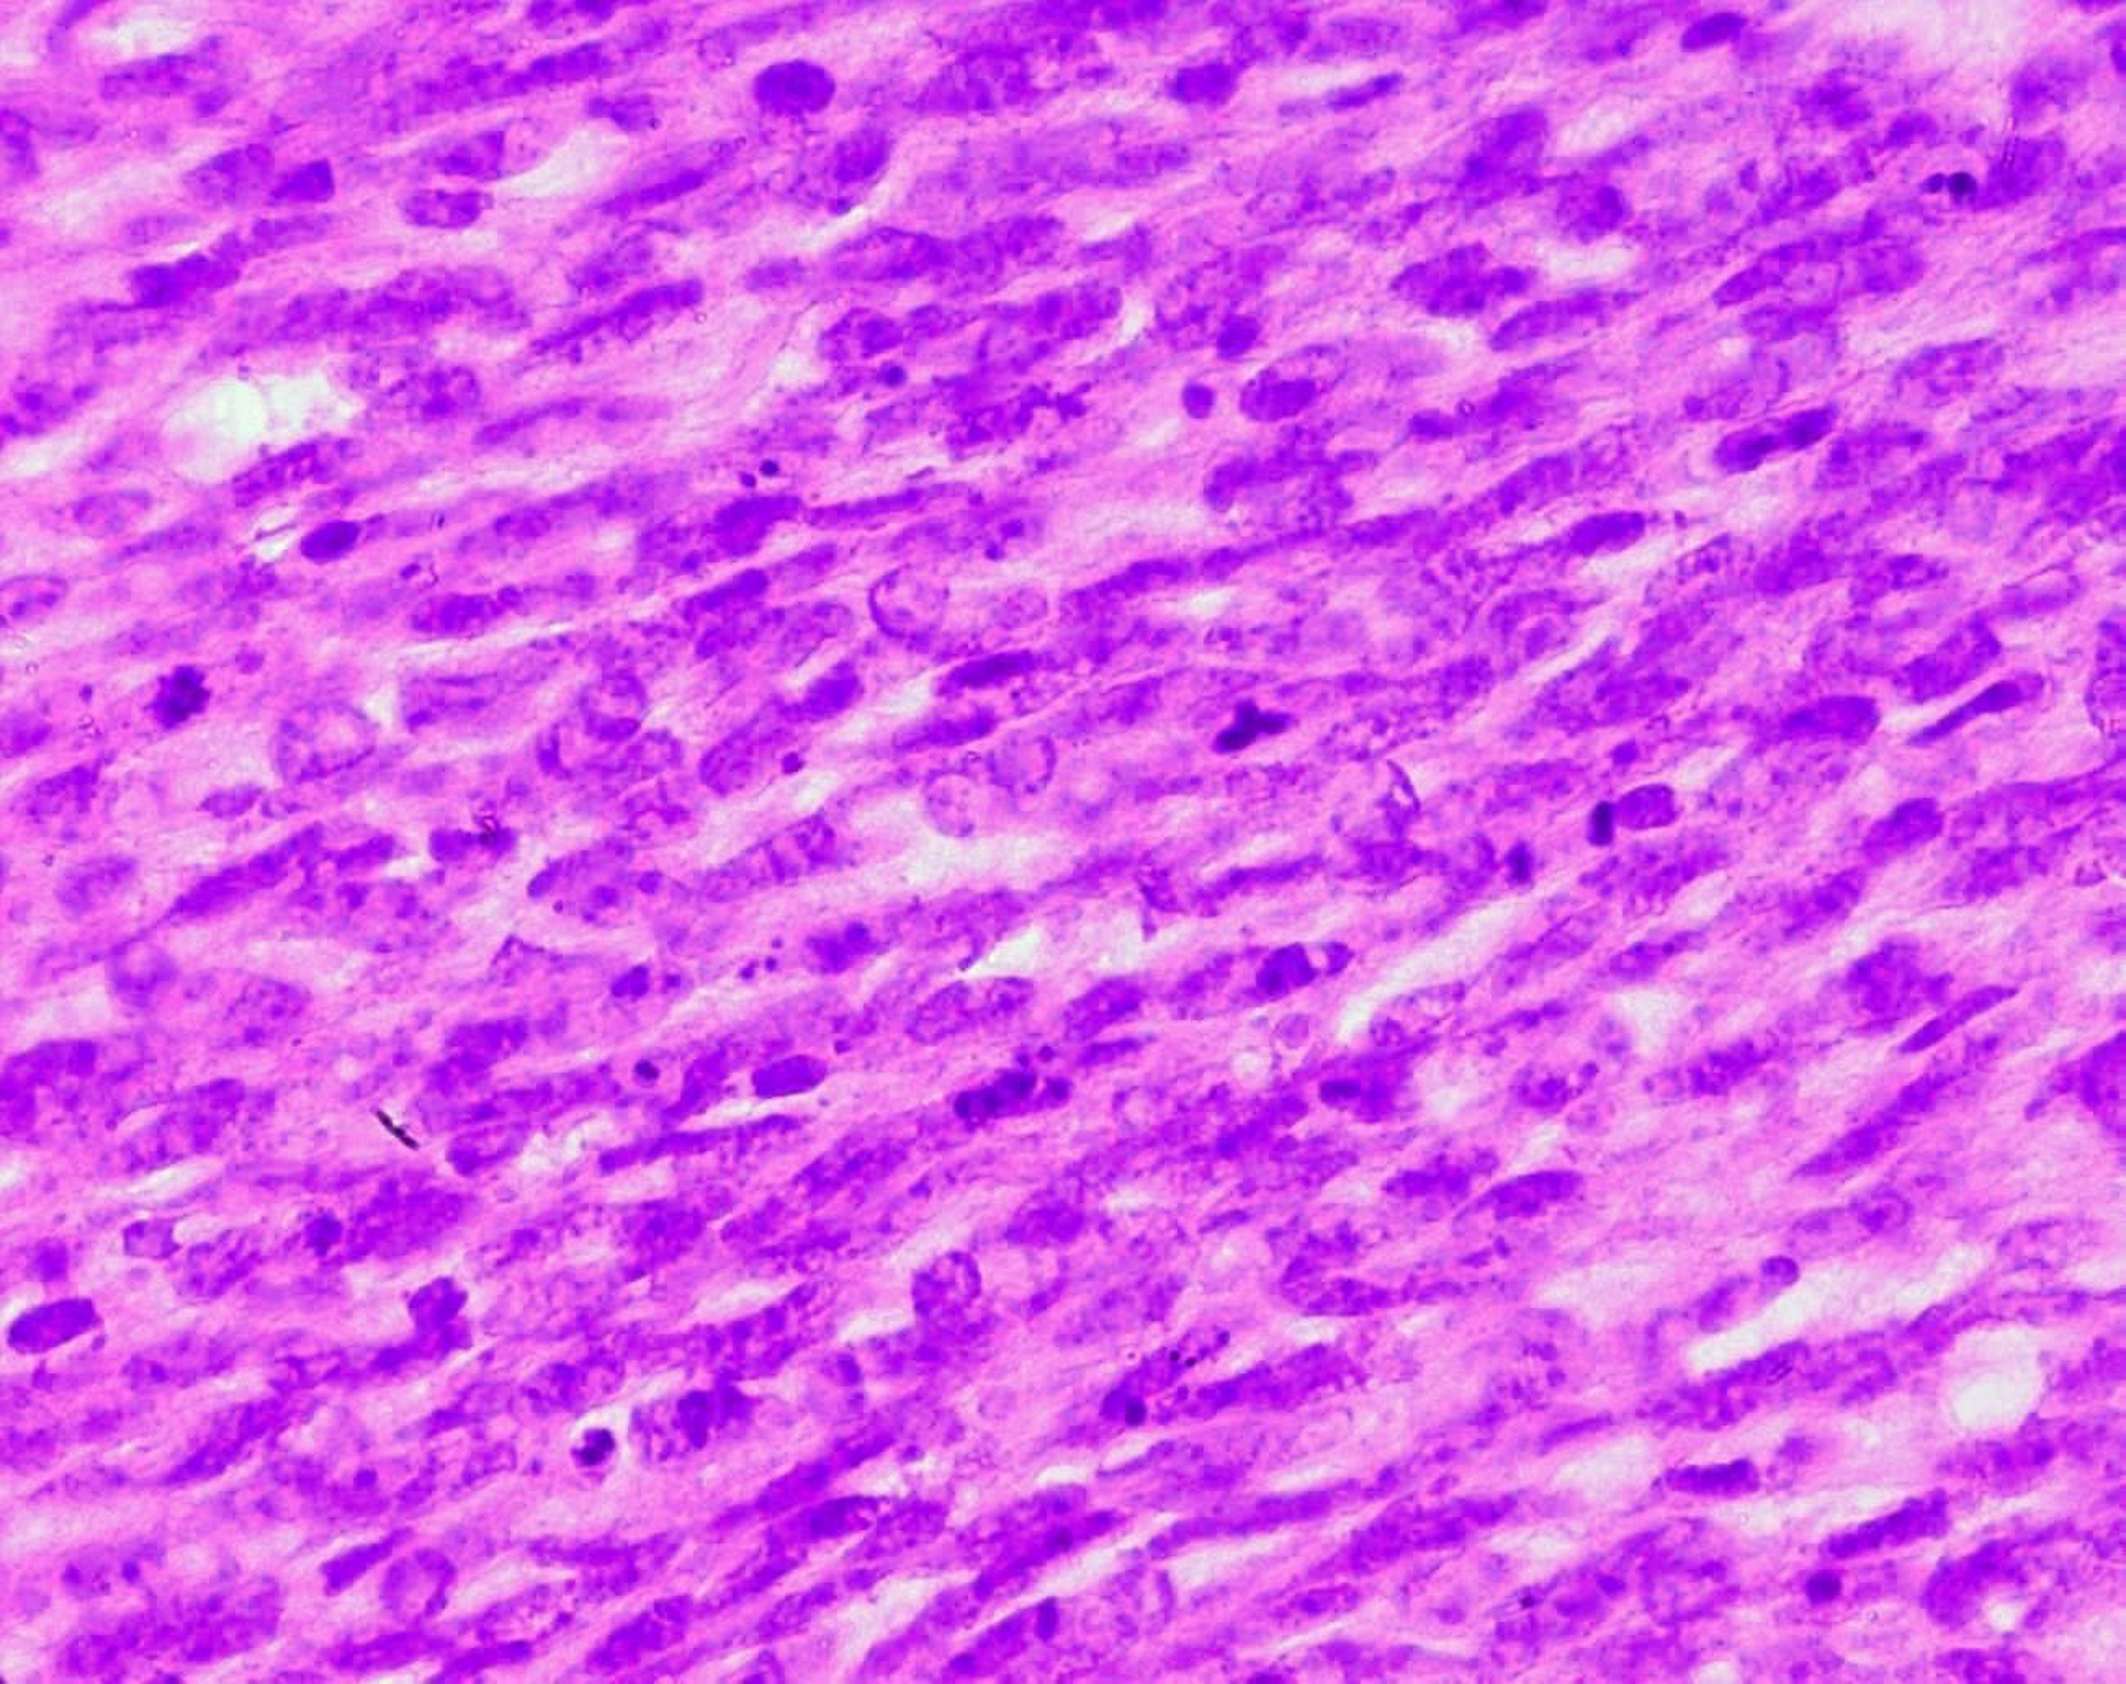

Surgical treatment was primarily applied in all cases, consisting in lumpectomy in 21 cases and total mastectomy in 5 cases (4 malignant PTs and 1 borderline PT). Frozen-section analysis was undertaken in 19 cases. It was concordant with final histology in 14 cases. Three out of the 5 remaining cases were benign PTs at the final histology and assessed as fibroadenomas in frozen-section analysis. One borderline PT at the final histology was assessed as malignant PT at frozen-section analysis and one borderline PT was incorrectly assessed as benign at frozen-section analysis. On gross appearance, tumors ranged in size from 1.5 to 40 cm (mean 7.8 cm), 14 tumors were larger than 5 cm. The size range for benign, borderline, and malignant tumors was 1.5 to 40 cm (mean: 7.4 cm), 1.7 to 15 cm (mean: 7.5 cm), and 3.6 to 23.4 cm (mean: 9 cm), respectively. On histological examination, 13 tumors were graded as benign (Fig. 3), 7 tumors as borderline (Fig. 4) and 6 tumors as malignant (Fig. 5).

![]() Click for large image | Figure 5. Stromal cells of a malignant PT showing marked nuclear atypia and frequent mitoses (HE x 400). |